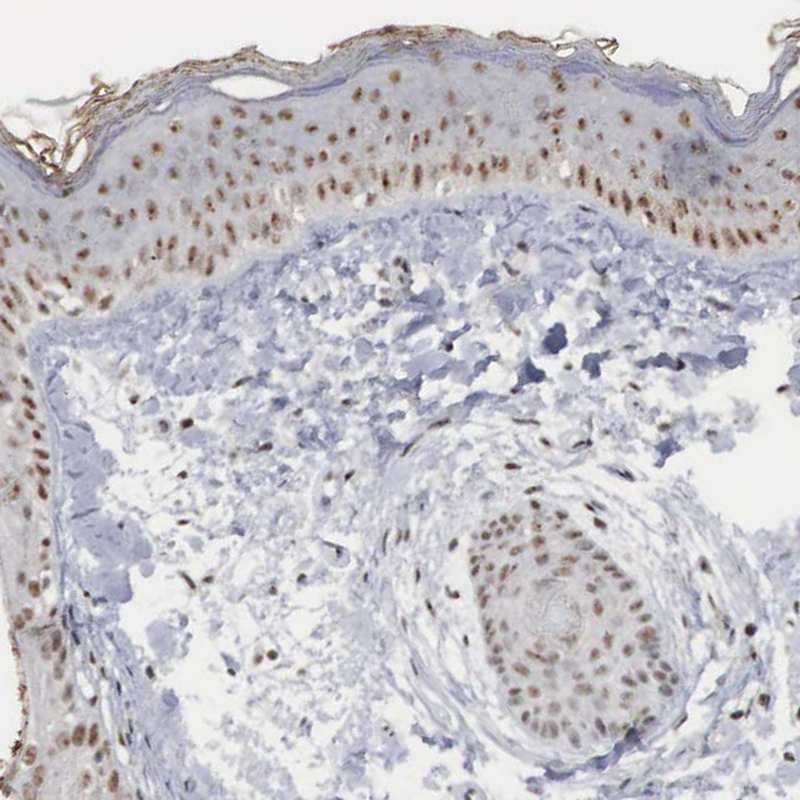

Immunohistochemical staining of human cerebral cortex shows moderate nuclear positivity in neuronal cells.